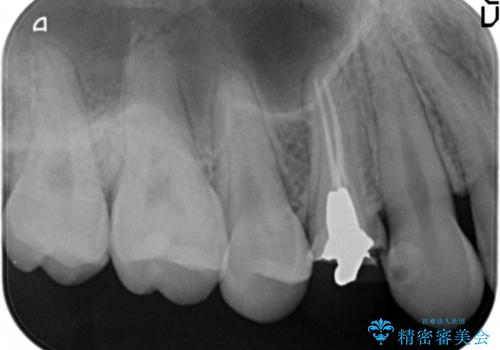

- 食事中に急に歯が折れ、周囲の歯も痛みだし治療を希望され来院されました。

ジルコニアクラウンによる咬合機能回復、根管治療を行い歯の痛みをとり長期的な予後の見込める治療を計画します。